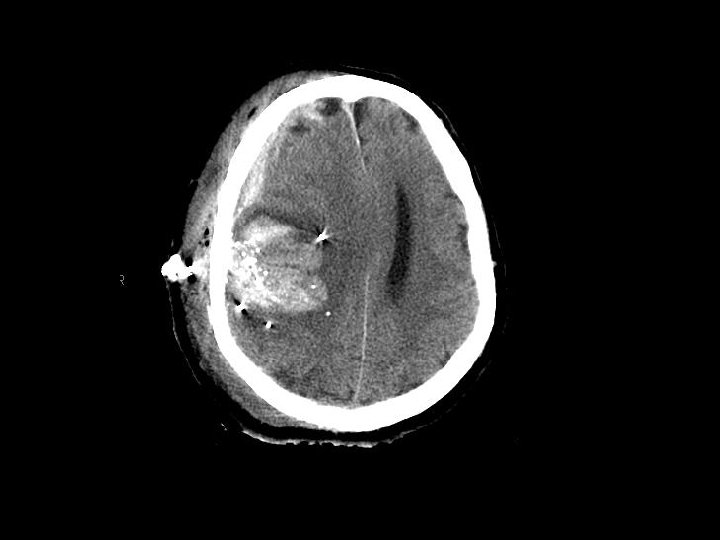

Vết thương thấu • Vết thương hỏa khí hoặc đâm • Gặp ở thành thị lớn • Chấn thương vượt qua đường giữa có kết quả điều trị kém • Vùng trước cung mày/mũi tăng nguy cơ nhiễm khuẩn